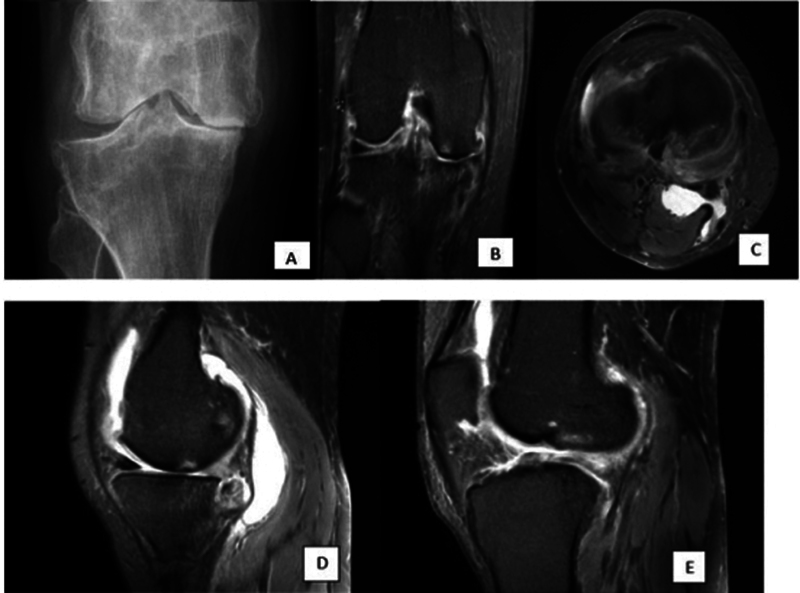

Background  Knee joint osteoarthritis (OA) is among the most prevalent degenerative diseases of the joints in the body. Various scoring system exists for grading OA, such as (1) magnetic resonance imaging (MRI) Osteoarthritis Knee Score (MOAKS), (2) clinical grading by Western Ontario and McMaster Universities Arthritis Index (WOMAC), and (3) X-ray grading of the Kellgren-Lawrence grading system (K-L). Objectives  To study MRI findings and MOAKS scoring of knee OA and correlation with WOMAC and K-L scoring. Setting and Design  Cross-sectional study in hospital population. Materials and Methods  A total 40 knee OA cases underwent an MRI of the knee. MOAKS scoring was done and compared with K-L grading and WOMAC scores. Statistical Analysis  Collected data were compiled systematically and interpreted using IBM SPSS statistics software 25.0. A p -value of less than 0.05 was considered significant. Results  The mean total WOMAC score was 9. K-L grade 2 was the most prevalent X-ray grade. Bone marrow lesion (BML) and cartilage loss in MOAKS score were greater in the medial femorotibial region. A moderate positive correlation was noted between the WOMAC score and K-L grade; full-thickness articular cartilage loss score at the medial femorotibial joint (MFTJ) and WOMAC score; partial-thickness articular cartilage loss score at lateral femorotibial joint (LFTJ) and WOMAC total pain score. No correlation was found between BML and pain severity score. Conclusion Higher WOMAC scores were associated with higher grades of K-L scoring and score of cartilage loss (partial and full thickness) of the MOAKS scoring system. The rest of the features of the MOAKS score (BML score, osteophyte, and synovitis) had no significant association with pain severity and K-L grading.

Abstract Image